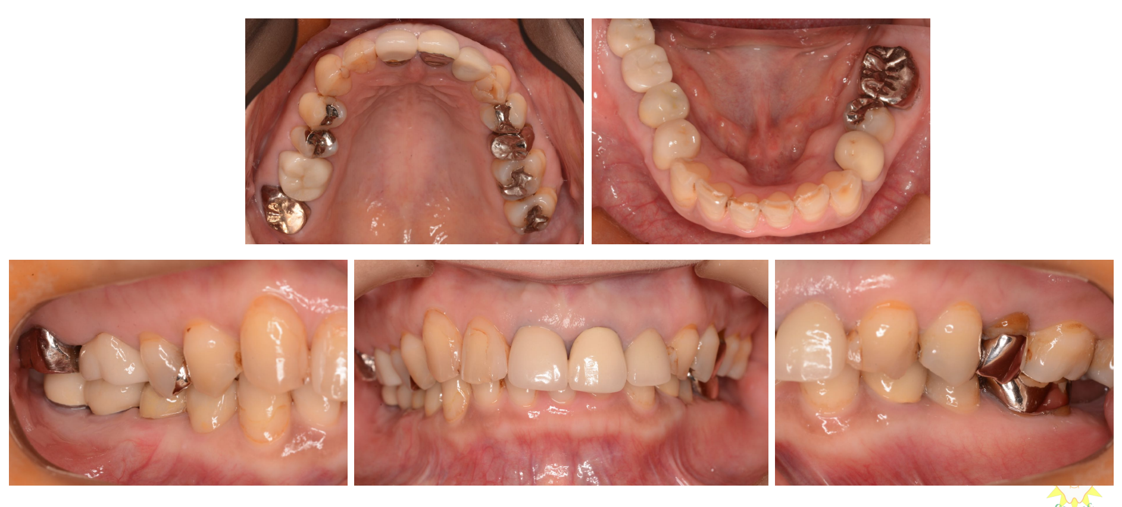

インプラント治療の症例6

(上下の歯が複数本ない・咬合崩壊)

治療前

治療後

| 診断名・主訴 | ①治療の続きをしてほしい ②インプラント希望 |

| 年齢 | 50歳 |

| 治療期間 | 3年間 |

| 治療内容 | インプラント治療 |

| 治療に用いた主な材料、設備機器 | 京セラFINESIAインプラント 上部構造:ジルコニアセラミック |

| 抜歯部位 | 右上8・6・2 左上5・6 |

| 治療費 | 約350万 |

| リスク・副作用 | 術後出血や腫れ |